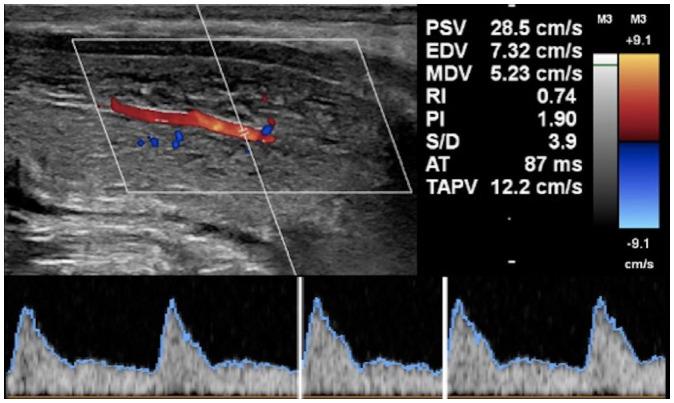

Penile emergencies are uncommon and can be categorized as having infectious, vascular, traumatic, or multifactorial etiologies. To facilitate early diagnosis and treatment during emergency, US and color Doppler imaging are imperative. US depicts hypoechoic collections regardless of the presence of air foci in infections like abscess and Fournier's gangrene. Color Doppler imaging is conducted to evaluate vascular conditions such as penile Mondor disease (PMD) and priapism. PMD is indicated by the absence of color flow and non-compressibility of dorsal penile vein. Priapism can be categorized based on cavernosal artery flow: high flow and low flow. In traumatic injuries like penile fracture, US reveals breach in tunica albuginea with hematoma. Peyronie's disease can be multifactorial in origin and the imaging is commonly visualized as thickening of the tunica albuginea and echogenic calcified plaques. Urethral injuries are urethral discontinuity with adjacent collection. Urethral calculus is visualized as echogenic focus with posterior acoustic shadowing. Therefore, effective collaboration between radiologists and urologists is required for appropriate initial diagnosis and prompt treatment.

阴茎急症并不常见,可分为感染性、血管性、创伤性或多因素病因。为便于在急诊时进行早期诊断和治疗,超声(US)和彩色多普勒成像必不可少。在诸如脓肿和福尼尔坏疽等感染中,无论是否存在气灶,超声均能显示低回声液性聚集。进行彩色多普勒成像以评估血管状况,如阴茎蒙多氏病(PMD)和阴茎异常勃起。阴茎蒙多氏病表现为阴茎背静脉无血流信号且不可压缩。阴茎异常勃起可根据海绵体动脉血流分为:高流量型和低流量型。在阴茎骨折等创伤性损伤中,超声显示白膜破裂并伴有血肿。佩罗尼氏病的病因可能是多因素的,影像学表现通常为白膜增厚和回声增强的钙化斑块。尿道损伤表现为尿道连续性中断并伴有相邻液性聚集。尿道结石表现为伴有后方声影的回声增强灶。因此,放射科医生和泌尿外科医生之间需要有效协作,以进行恰当的初步诊断和及时治疗。